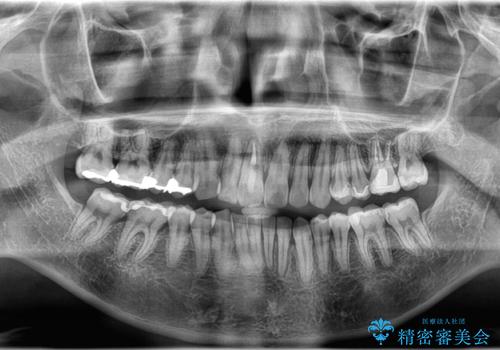

- 「上の前歯の捻じれと下の前歯のでこぼこを治したい」を主訴に来院された患者様です。

矯正検査の結果、非抜歯で矯正可能だったためインビザラインで治療を行いました。

アーチの拡大とIPRで叢生を改善いました。

11ヵ月で矯正を終える事ができ患者様も大変ご満足されていました。